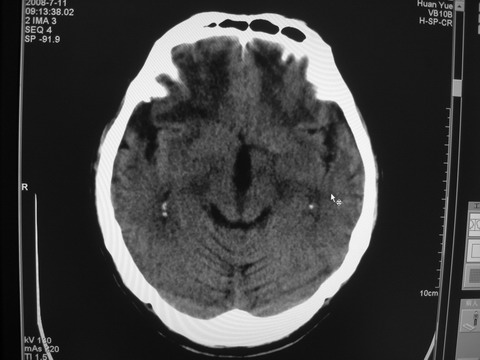

患者 男 69岁 头晕头痛不适

多发病灶,指状水肿,首先诊断转移瘤。

多个结节并周围大面积水肿区,多考虑多发性脑转移瘤

小病灶、大水肿,病灶多发,首先考虑多发转移瘤;建议查原发灶。

额顶叶多发小病灶、大水肿,首先考虑多发转移瘤;建议查原发灶

脑内多发病灶,小病灶,大水肿。

典型转移性肿瘤。

应进一步检查,查找原发病灶。

结果 : 该患者结肠癌病史5年 考虑脑转移